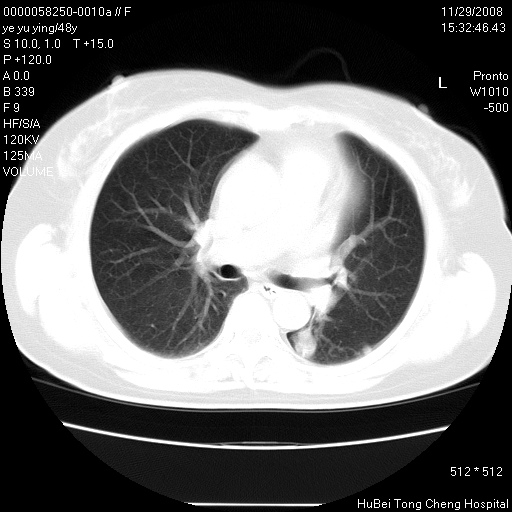

以下是引用huenhao在2008-11-29 22:11:00的发言:[br]脂肪肝,胆囊结石。左肺病灶建议定期复查。

以下是引用liuyue在2008-11-30 5:44:00的发言:[br]1.左肺病变,首先考虑感染性病变,转移待排;建议治疗后复查。[br]2.肝脏密度普遍减低,考虑与化疗有关。[br]3.胆囊结石.